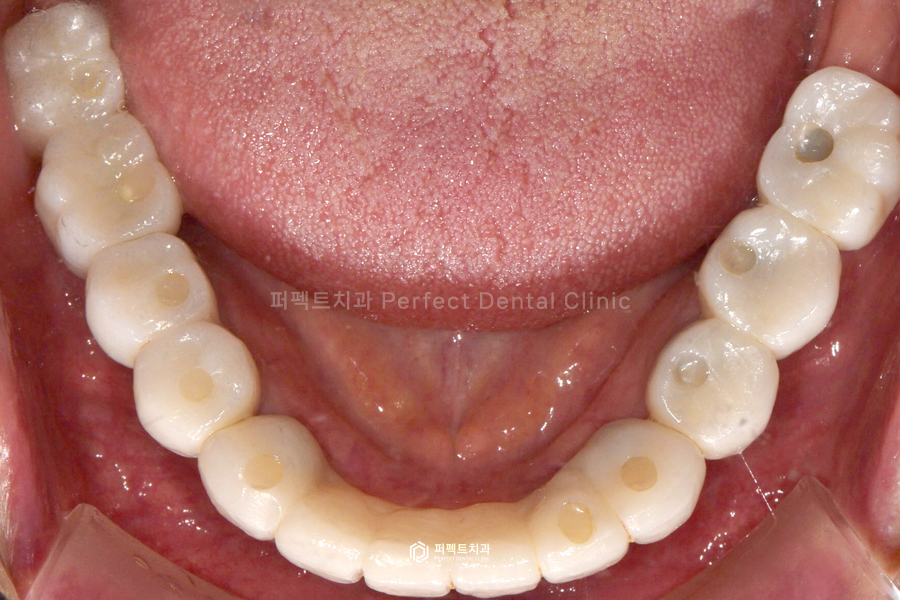

전체적으로 정리해서 말씀을 드리면 아랫니의 경우 흔들리는 앞니는 전부는 전부 발치하고, 임플란트를 10개 식립하였습니다. 윗니는 너무 흔들리는 앞니 두개만 발치를 했고, 나머지는 깨끗하게 신경치료를 한 후, 지르코니아 크라운으로 씌워서 사용하기로 하였는데요. 앞니는 걸어서 사용하는 브릿지로 완성하고 나머지는 싱글 크라운으로 하나씩 제작해서 사용할 수 있도록 해드렸습니다.

위 사진을 보시면 전체 신경치료 후 지르코니아 크라운을 씌웠고, 아래는 임플란트 10개를 식립 후 위에와 마찬가지로 지르코니아 크라운으로 완성을 했습니다.